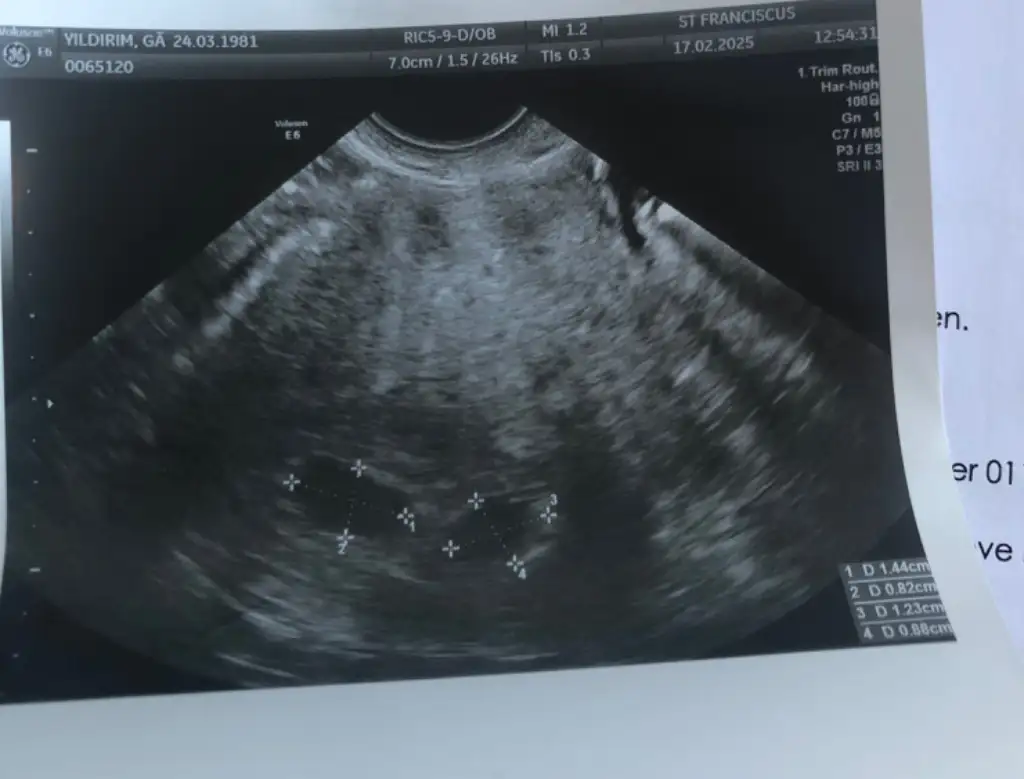

Ölçüleri iyi görünüyor telaş etme lütfen. Bu bölüm çok zor geçiyo işte yaKeseler böyle göründü ama içini göremesik